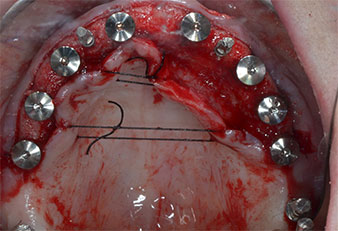

Drei Jahre später war es Zeit für eine gleichartige Oberkieferprothese. Basierend auf der DVT-Planung wurde durch Verwendung kurzer Implantate eine Sinusaugmentation vermieden und die geplanten Implantatpositionen wurden mit einer Bohrschablone auf den Kieferkamm übertragen (Abb. 1 und 2).

Abb. 2: Nach dem Kieferkammschnitt und der Präparation der Mukoperiostlappen werden die Implantatpositionen auf den Knochen übertragen.